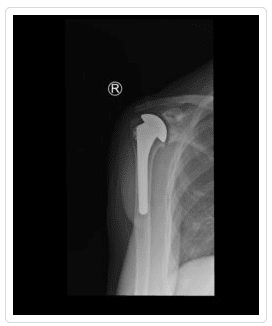

In this procedure, arthritic joint surfaces and the damaged ball-and-socket joint are replaced with artificial components. The ball is replaced with a metal ball that is secured into the arm bone (humerus) with a stem. The socket or glenoid is resurfaced for a smooth fit with a prosthetic made of high-density polyethylene. The shoulder replacement surgery is highly successful for the majority of patients, who experience pain relief and improved function.